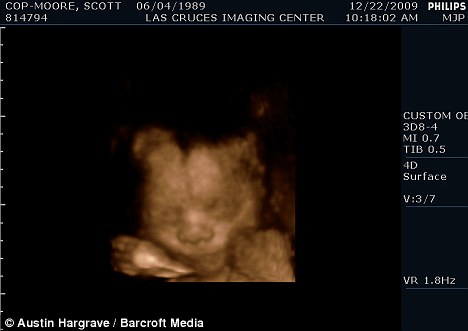

掃描顯示斯科特懷的是個男孩

現年30歲的斯科特·穆爾和丈夫托馬斯來自美國加利福尼亞州,兩人原先都是女性,托馬斯接受過變性手術后成為真正的男子漢,斯科特仍然留有一些女性器官并持有女性出生證明,所以他們的婚姻是合法的。目前他們已經知道未出生的孩子是個男孩,準備給他取名“邁爾斯”。

2009年6月,斯科特從一名男性朋友那里取得精子,并通過人工受精成功懷孕。他打算在當地的醫(yī)院自然分娩。